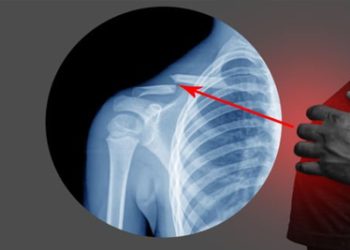

Broken CollarboneDiagnosis of a Broken Collarbone 12 months agoDiagnosis of a Broken Collarbone Diagnosis of a...